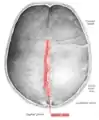

Human adult skull from above.

Human adult skull from above. Sagittal suture labeled at center.

The sagittal suture is formed from the fibrous connective tissue joint between the two parietal bones of the skull.[1] It has a varied and irregular shape which arises during development.[1] The pattern is different between the inside and the outside.[1]